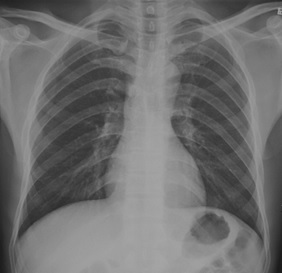

試題:根據(jù)下圖請(qǐng)做出正確診斷

A.正常胸片

B.肺門淋巴結(jié)腫大

C.肺炎

D.主動(dòng)脈型心(靴型心)